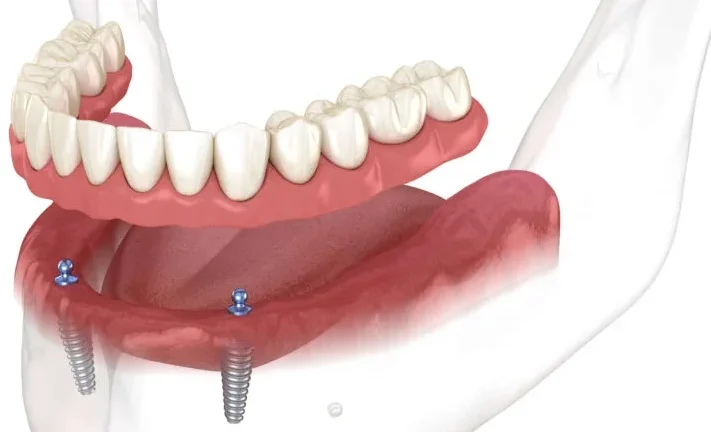

Comprehensive Full Arch Restoration with Minimal Implants

The All-on-4 implant technique revolutionizes full arch dental restoration by using just four strategically placed implants to support a complete set of fixed, non-removable teeth. This method is particularly beneficial for patients with significant tooth loss or those seeking a more cost-effective solution compared to traditional full arch implants.

Experience Stability and Comfort with Secure Dentures

Implant-supported dentures offer a stable and secure alternative to traditional removable dentures. Anchored to dental implants, these dentures provide enhanced functionality and comfort, allowing you to eat, speak, and smile with confidence.